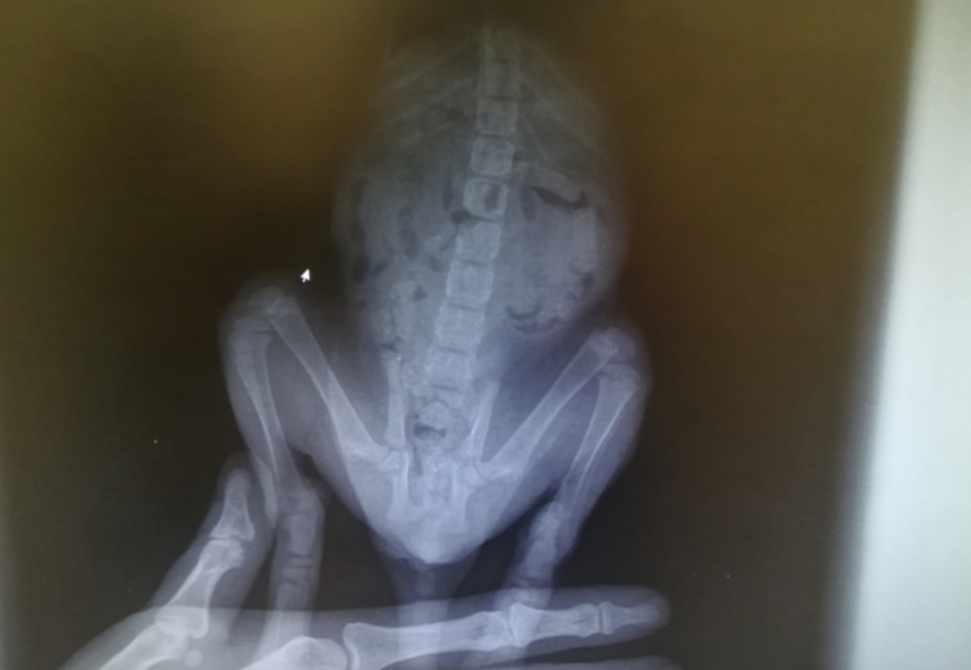

2 miesięczny kotek potrącony przez samochód. Kociak ciągnął tylne łapki, wykazywał silną bolesność podczas badania palpacyjnego. Po kroplówce maluch na cito zawieziony na RTG z podejrzeniem złamania w obrębie kości miednicy/ kręgosłupa. Na szczęście badanie nie wykazało złamań - wygląda na to, że maluszek miał dużo szczęścia. Co prawda w obrębie kości łonowej obraz rtg mocno zacieniony przez masy kałowe, więc jeśli niedowład łapek nie ustąpi, zrobimy kolejne rtg. Kotek ma silną krwawo - śluzową biegunkę. W związku z tym zrobiliśmy test na panleukopenię - na szczęście wyszedł ujemny. Maluch jest brudny, zabiedzony, strasznie głodny i spragniony... O dziwo bez świerzba i pcheł, nie wiemy jak z życiem wewnętrznym. Na dokładkę mamy też zaawansowany koci katar. Oczka są w bardzo złym stanie... ulicy maluch by nie przeżył! Teraz jest już bezpieczny w domu tymczasowym. Walczymy! Bardzo gorąco prosimy Was o wsparcie. Przed nami kolejne badania, długotrwałe leczenie kociego kataru, nie wiemy co jeszcze wyniknie po drodze. Kociak wymaga zbilansowanej diety i dokarmiania Convalescentem. Jeśli możecie dorzucić grosik - prosimy bardzo serdecznie.